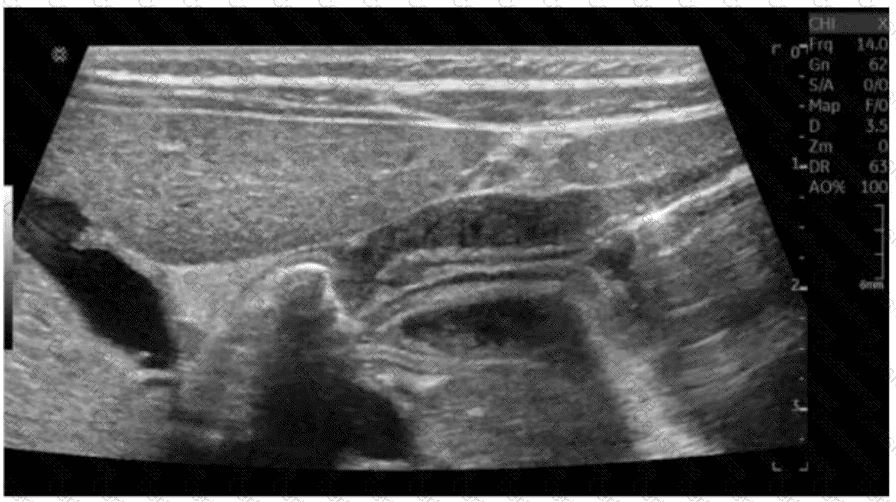

The ultrasound image shows a classic longitudinal view of a markedly thickened pyloric muscle with an elongated pyloric channel. This finding is consistent with hypertrophic pyloric stenosis (HPS), a condition most commonly seen in male infants between 2 and 8 weeks of age.

Sonographic diagnostic criteria for HPS:

Pyloric muscle thickness ≥ 3 mm

Pyloric channel length ≥ 15–17 mm

“Cervix sign” or “target sign” (transverse view)

Failure of gastric contents to pass through the pylorus on real-time imaging